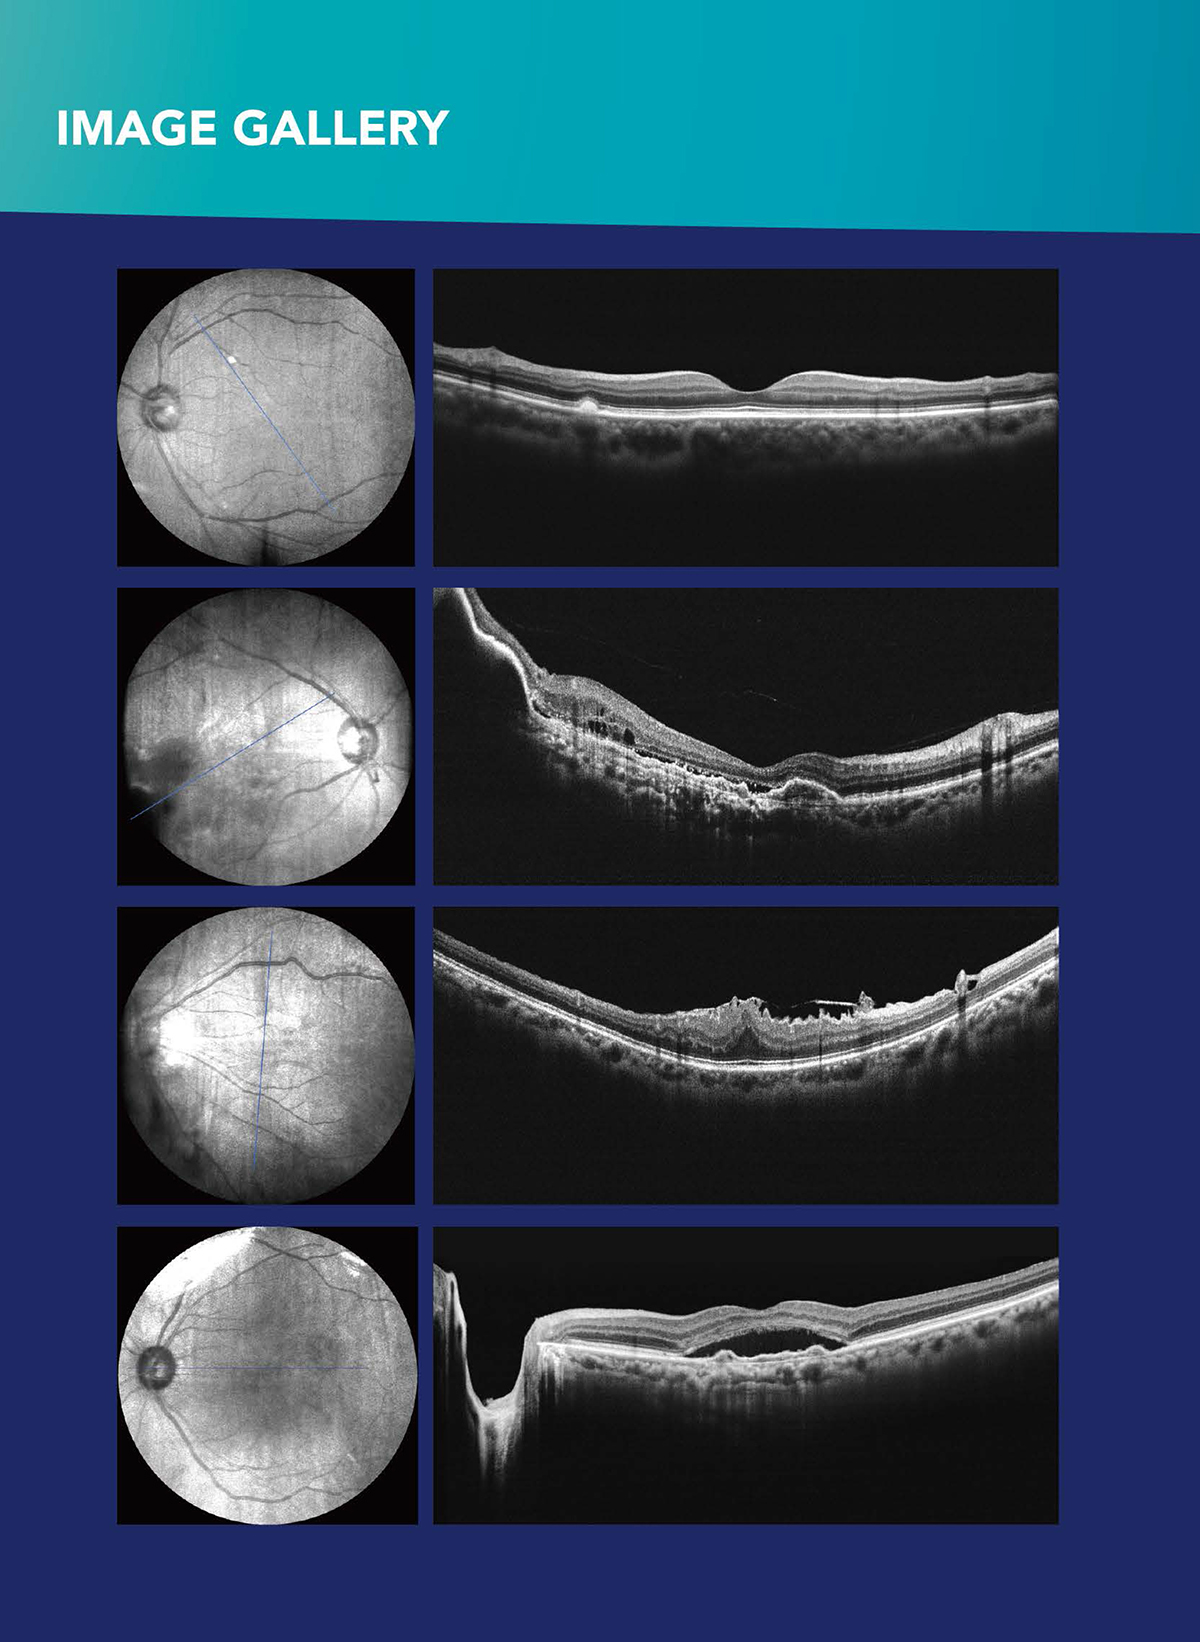

Optical coherence tomography imaging of macular oedema British

From bjo.bmj.com

Optical coherence tomography imaging of macular oedema British Optical Coherence Tomography Ophthalmology the relatively fast translation of optical coherence tomography (oct) from an optical measurement technology to a standard of care in. optical coherence tomography (oct) is a noninvasive imaging method that eye care specialists use to produce cross. optical coherence tomography. Optical Coherence Tomography Ophthalmology.